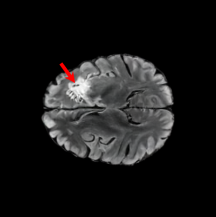

6.3 When does X-Diffusion Fail?

To see when and how X-Diffusion fails, we conducted an experiment on healthy brains (no tumour) using the IXI dataset, by running an X-diffusion trained on the BRATS brain tumor dataset. Our X-Diffusion achieved a PSNR of 35.86 dB on the IXI dataset despite being trained on the BRATS dataset. We then ran the tumour segmenter on the set of 582 healthy scans and corresponding generated MRIs. The segmenter predicted tumours in 9.9% of the real healthy brains and in 11.3% of the generated brain MRIs. Some of these tumor hallucination examples from X-Diffusion generation are shown in Figure 9.

This shows how the generated MRIs indeed preserve the tumour information and can act as an affordable and informative pseudo-MRI, before conducting an actual costly MRI examination in hospitals. Given that our model has been trained on brain scans all with tumours, we expect to see hallucinations of tumours in healthy scans. We report two cases of failure of our model in Figure 16. Hallucinations of tumours on healthy samples represent 2% of the test set.